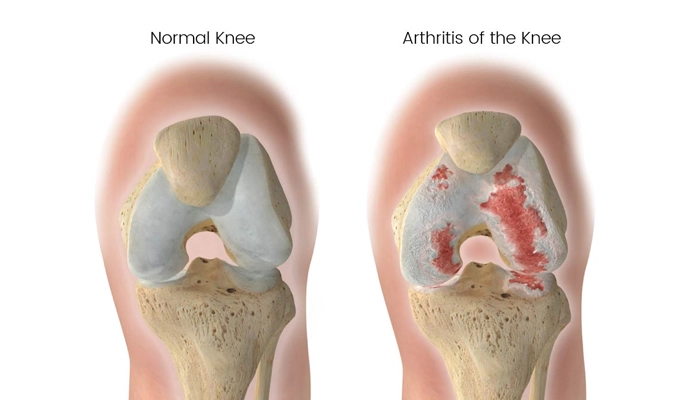

آرتروز زانو با تخریب غضروف مفصل زانو آغاز شده و در صورت عدم درمان میتواند پیامدهای جدی به همراه داشته باشد. در این مقاله به بررسی خطرات آرتروز زانو و راههای پیشگیری و کاهش این خطرات میپردازیم.

- تغییر شکل مفصل: در موارد پیشرفته، تخریب غضروف ممکن است باعث تغییر شکل زانو شود.